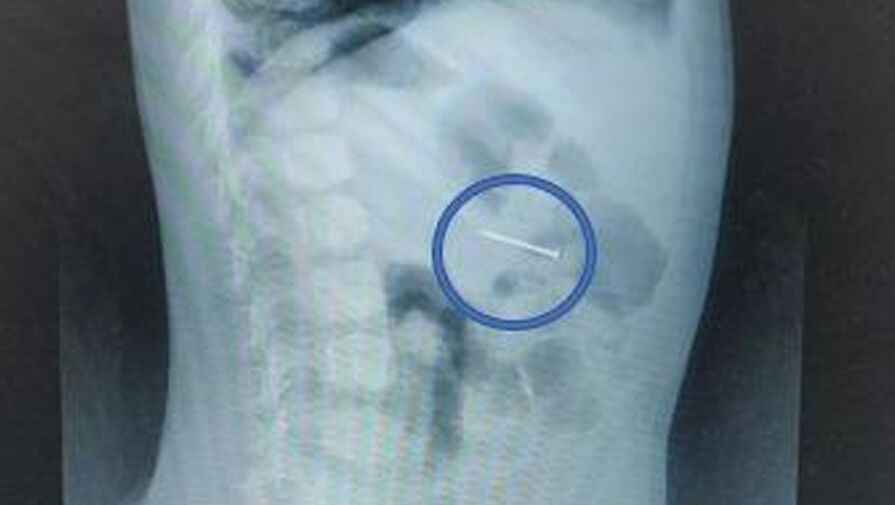

«Своевременно начатое вмешательство помогло избежать серьезных последствий. Сперва мы сделали рентгенографию – она подтвердила наличие гвоздя в желудке, а после выполнили гастроскопию: с помощью эндоскопических щипцов аккуратно захватили гвоздь за острый конец и извлекли его через ротовую полость», — поделился врач-эндоскопист Руслан Мусаев, добавив, что манипуляция заняла около 20 минут.